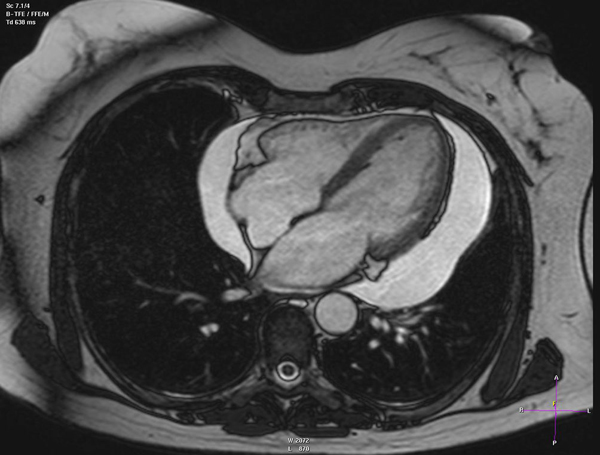

3- در دوران کرونا احتمال ابتلا به بیماری هایی که با مکانیسم ایجاد "لخته خون" یا " ترومبوز " ایجاد می شوند ، افزایش پیدا می کند. بیماری هایی مانند "سکته قلبی" ، "سکته مغزی" ، "ایجاد لخته خون در وریدهای عمقی پا DVT "و "آمبولی ریه" .

هر کدام از این بیماری ها به مراتب خطرناک تر از کرونا و ابتلا به بیماری های ویروسی هستند و خطر مرگ و میر و ناتوانی دایمی با این بیماریها قابل مقایسه با کرونا نیست. لذا لازم است در صورت بروز علایم هر کدام از این بیماریها هر چه سریعتر با اورژانس 115 تماس بگیرید.